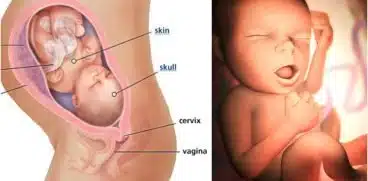

- Sarcina pe săptămâni

- Pregătirea nașterii

- Naștere naturală